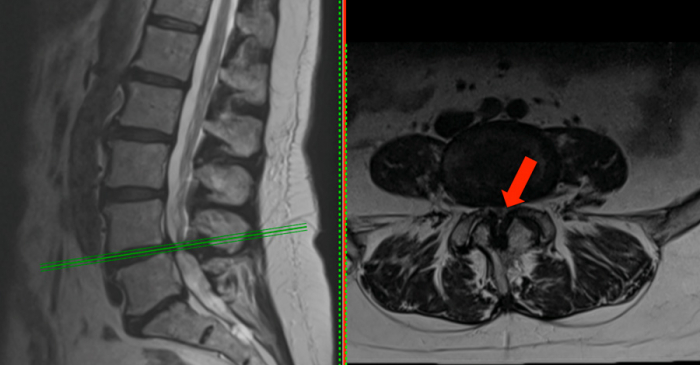

Disc herniation / Bulging disc

Bulging disc is one of the most common findings on spine imaging, MRI or CT scan. I am often asked if it is the cause of the neck or low back pain and whether it is dangerous and needs to be treated.